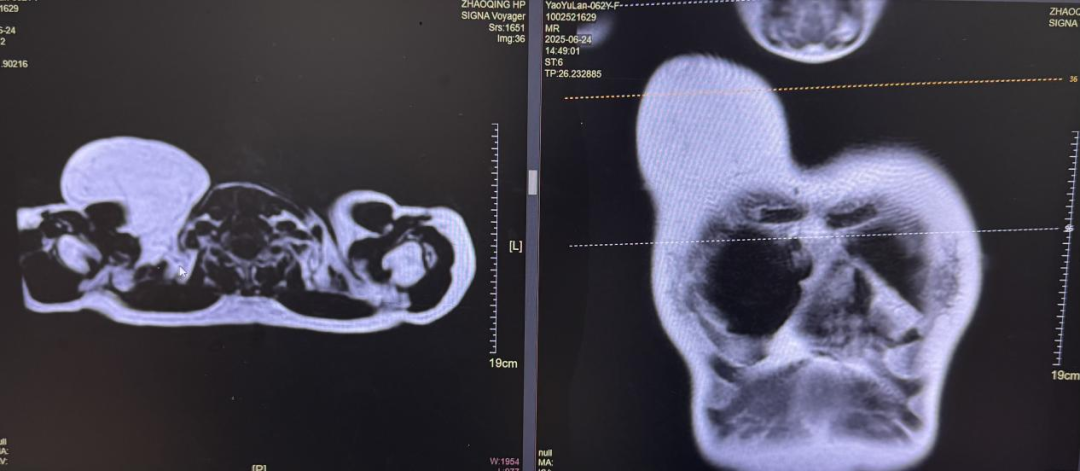

原來,困擾Y女士多年的,是個直徑近20cm的巨大脂肪瘤,更讓她頭疼的是,瘤子位置特殊,長在乳房上方,緊鄰肌肉和神經,而傳統(tǒng)開刀手術不僅要在胸部留下一道十幾厘米的"蜈蚣疤",還可能因損傷周圍神經血管組織。

傳統(tǒng)手術會在瘤體表面皮膚開個大大的切口,而目前的單孔腔鏡技術,則可以通過腋窩入路,切開一個約6cm的小口,置入單孔腔鏡裝置,借助高清鏡頭和精細器械,順著組織間隙找到瘤子,在避開周圍血管肌肉組織的情況下,像剝石榴一樣把20cm的瘤子完整"掏"出來。

由于瘤子太大,黃主任采用逆序法游離胸大肌表面筋膜,再沿腫瘤包膜分離皮下及腫物間隙,精準保護周圍重要結構。當瘤子完全游離后,采用類似助產士的分娩手法,將瘤子整體牽引推拉,從6cm的切口取出。